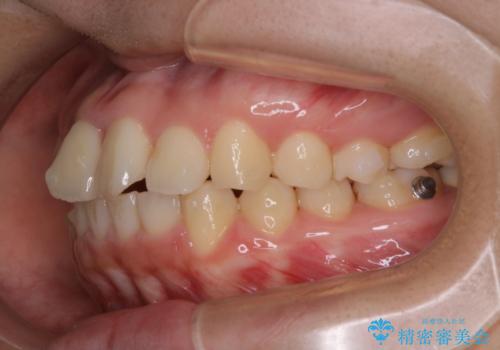

- 前歯が捻転していることを主訴に来院された方です。元々は部分矯正をご希望されていましたが、噛み合わせ等総合的に治療していくためインビザラインにて全顎的に治療を行うこととしました。

元々は上の前歯部の捻転のみの治療をご希望されていましたが、下の前歯もがたつきがあることや噛み合わせがかなり深いことを説明しました。後戻りのリスクを抑えるために全顎的な治療をご提案しました。

捻転していた上顎前歯部の仕上がりにこだわり、何度か修正を行ったため、満足のいく仕上がりになったと大変喜んでいただけました。